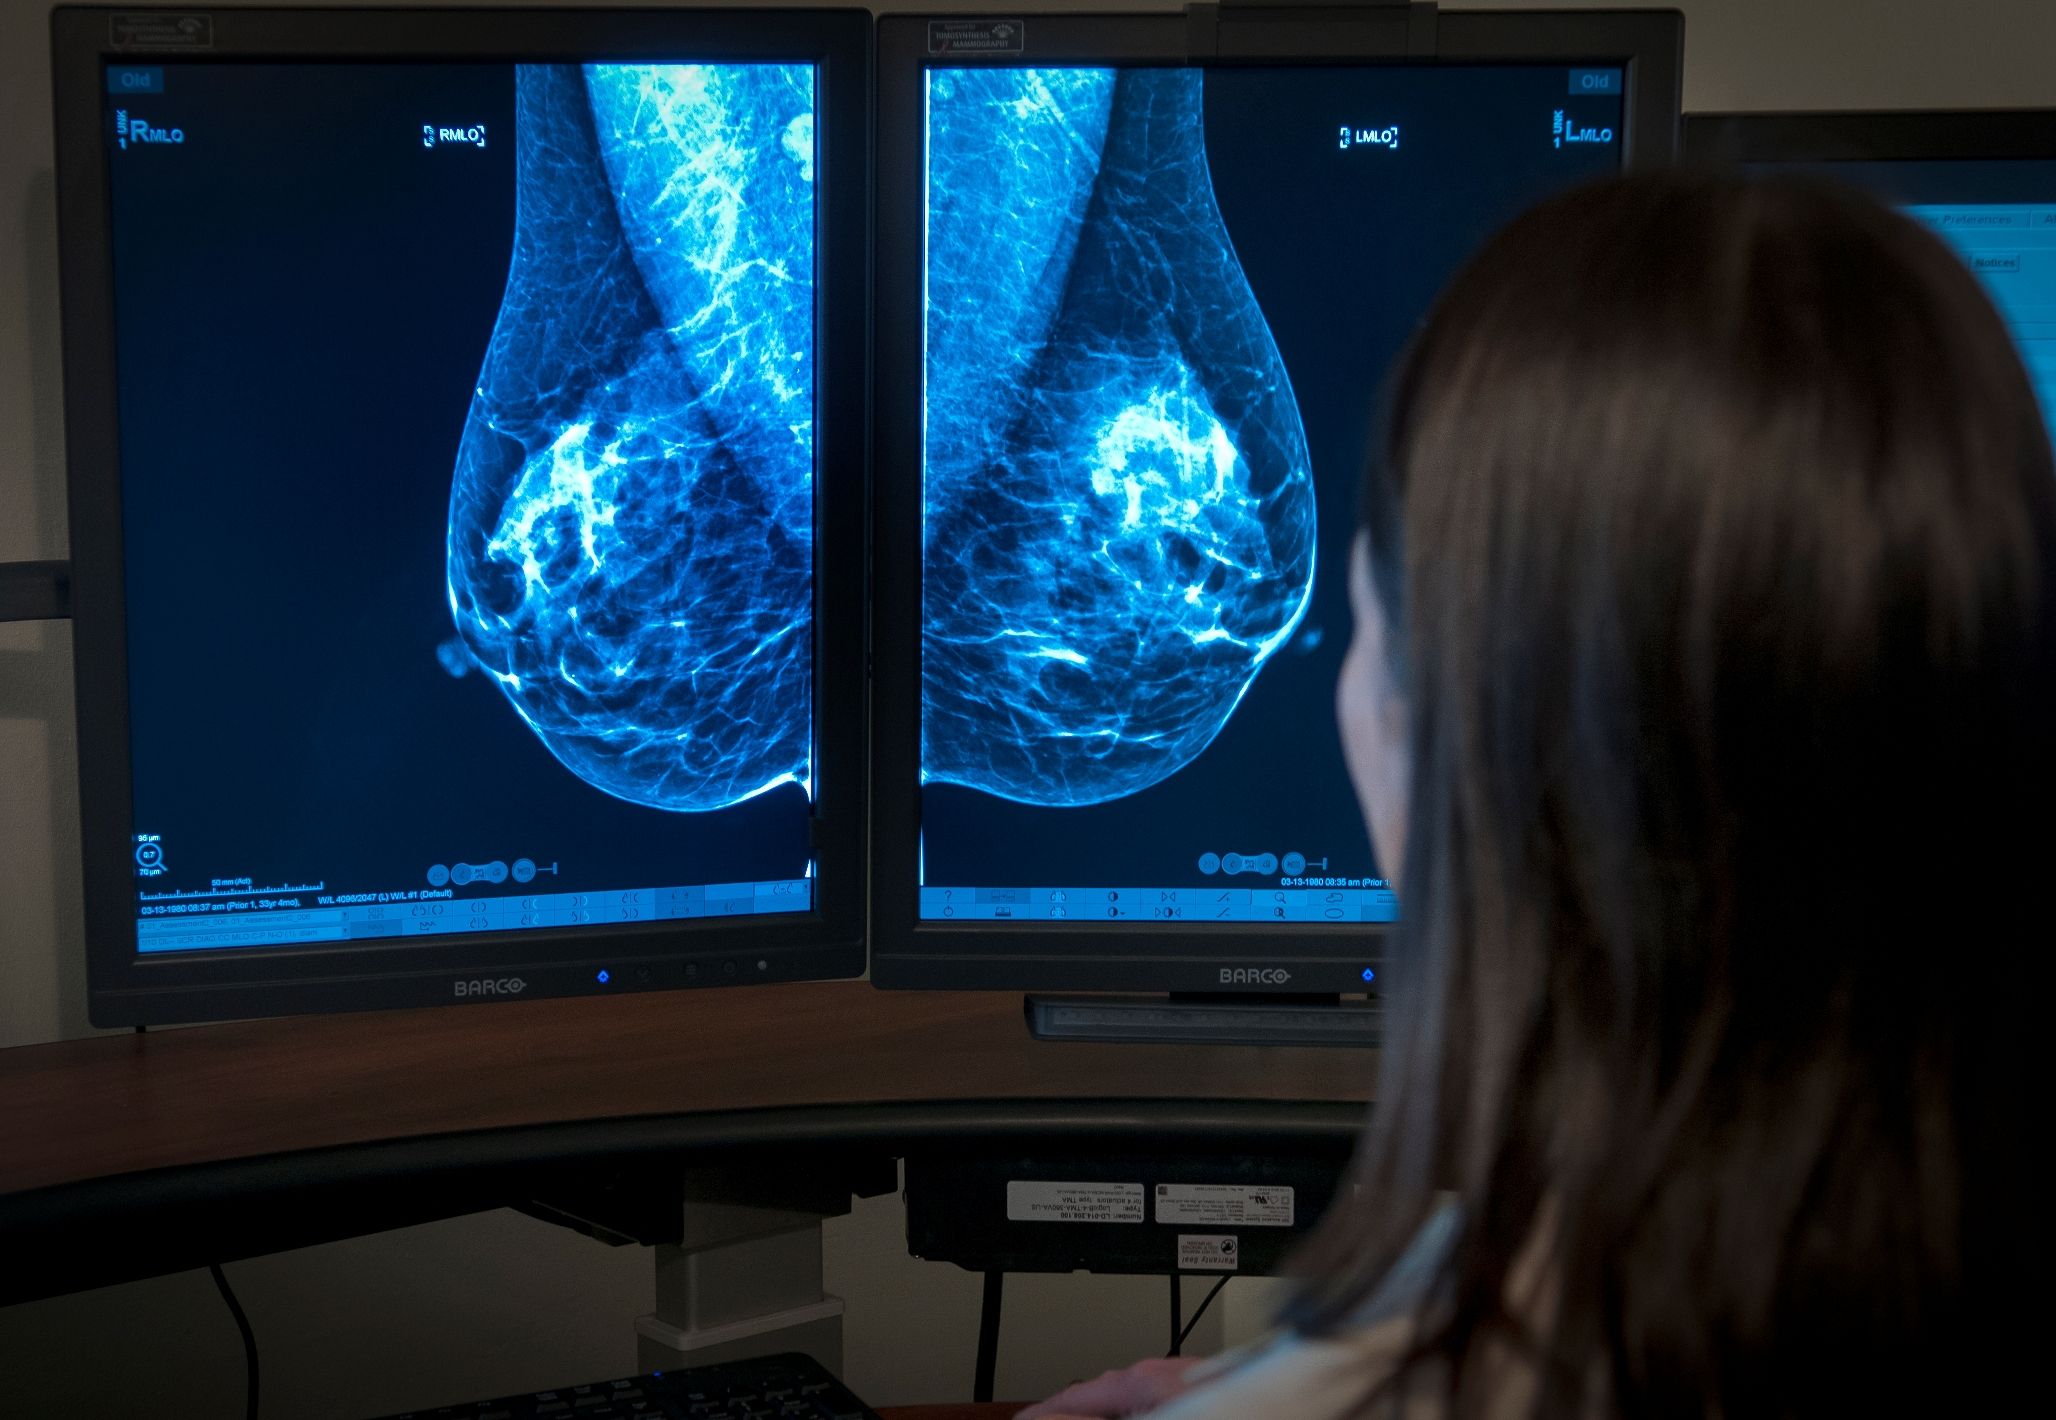

Цифровая

Суть цифровой диагностики аналогична рентгенографическому исследованию. Главное отличие заключается в том, что при цифровом обследовании изображение не фиксируется на пленке, а выводится на экран портативного монитора.